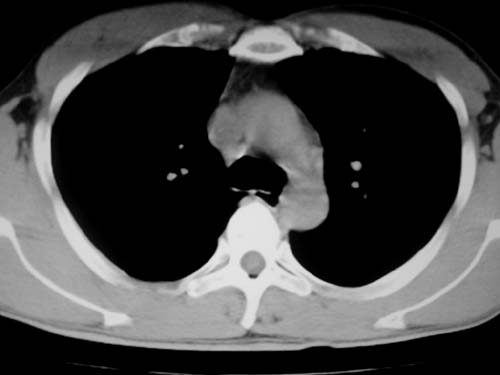

标题: CT19540: 31岁。自述结核性胸水治疗两个月后,在外院拍x线发 [打印本页]

标题: CT19540: 31岁。自述结核性胸水治疗两个月后,在外院拍x线发

右侧胸壁结节状软组织影伴相应肺叶内受侵,伴右侧胸腔积液。考虑:结核性可能大。

1、炎性包块;2、右侧少量胸膜积液。

1、炎性病变,结核可能;2、右侧少量胸膜积液。

右侧胸壁结节状软组织影伴相应肺叶内受侵,伴右侧胸腔积液,结合临床,首先考虑结核。

考虑结核性胸膜炎,胸膜肥厚,不除外胸膜间皮瘤可能,建议复查。

支持结核,胸膜间皮瘤不排除.

1)考虑右侧结核性胸膜结节。2)右侧胸膜增厚+包裹性胸腔积液。

结核性脓胸、肺内结核?